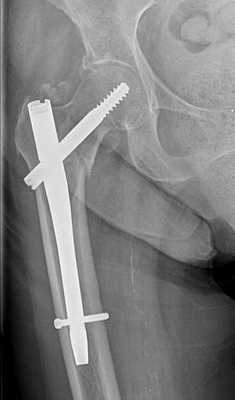

Удаление стержня (штифта) после операции

Внутрикостными (интрамедуллярными) стержнями с блокированием винтами или, как еще их называют, штифтами выполняют фиксацию переломов трубчатых костей, а в частности поперечных и винтообразных переломов с небольшим количеством отломков и осколков. Также предпочтение для внутрикостного остеосинтеза отдают ввиду скорости операции, миниинвазивности и малой травматичности операции. Стоит сказать, что фиксация стержнями очень хорошая и дозированную нагрузку на оперированную конечность разрешают давать уже через нечколько дней.

После успешной операции и сращения перелома, как правило, удаляют динамический винт и увеличивают нагрузку на конечность, для полного сращения перелома. Через 1 год после операции, когда перелом полностью сросся, в плановом порядке выполняется удаление винтов и стержня.

Почти всегда операция по удалению стержня не занимает более 30 минут, Удаление происходит с использованием подобных инструментов как и при установке.

Сложности при удалении стержня могут возникнуть, он установлен некорректно. Либо резьба и шляпки винтов сорваны. В таком случае нужно будет высверливать винты и стержень.